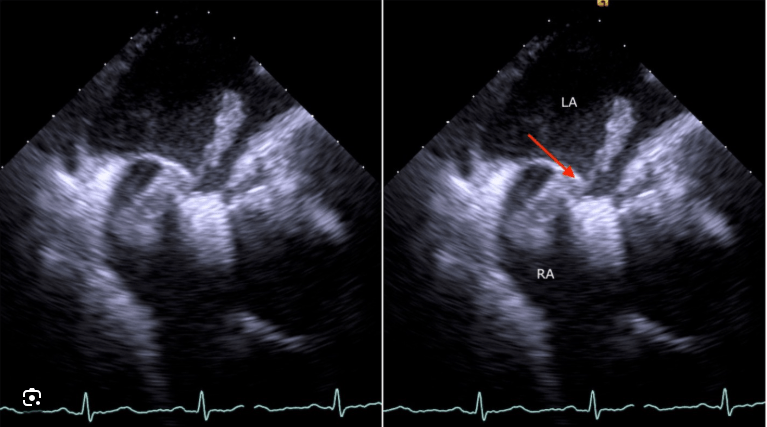

Clot in transit through a PFO

On echo, this finding defined by RV dyskinesis sparing the apex is suggestive of PE

McConnell's sign